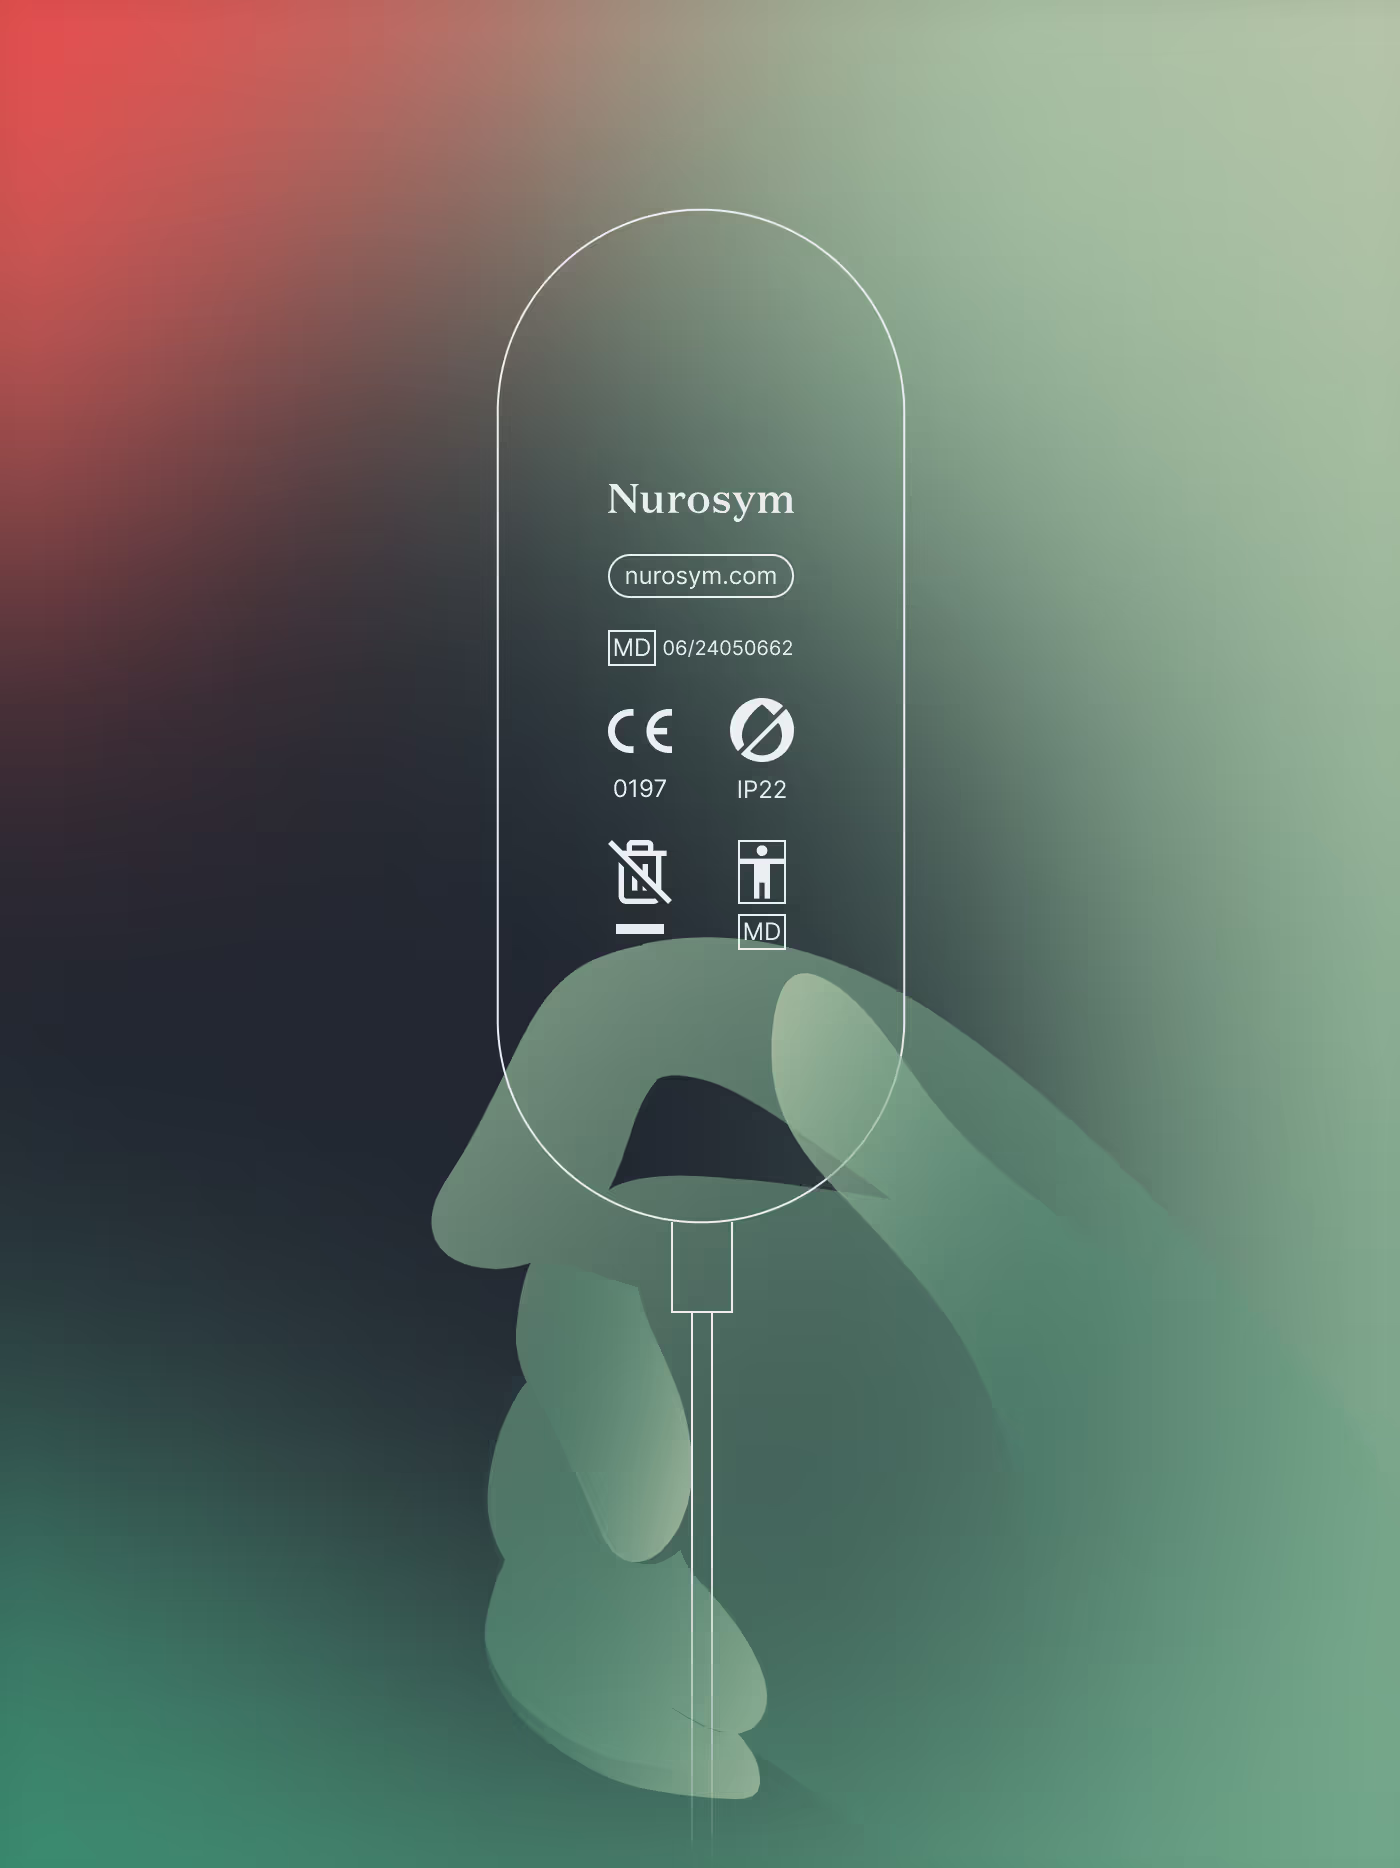

Certified and Proven Therapy

Auricular Vagal Neuromodulation Therapy™ is a proprietary, medically certified solution.

Clinically Validated, Safe, and Regulated

Clinically Regulated for Safety

AVNT™ is regulated to the highest standards, ensuring clinical-grade safety for patients and practitioners.

Compact Clinical-Grade Therapy

A palm-sized device delivering powerful, clinical-grade vagal neuromodulation for precise therapy.